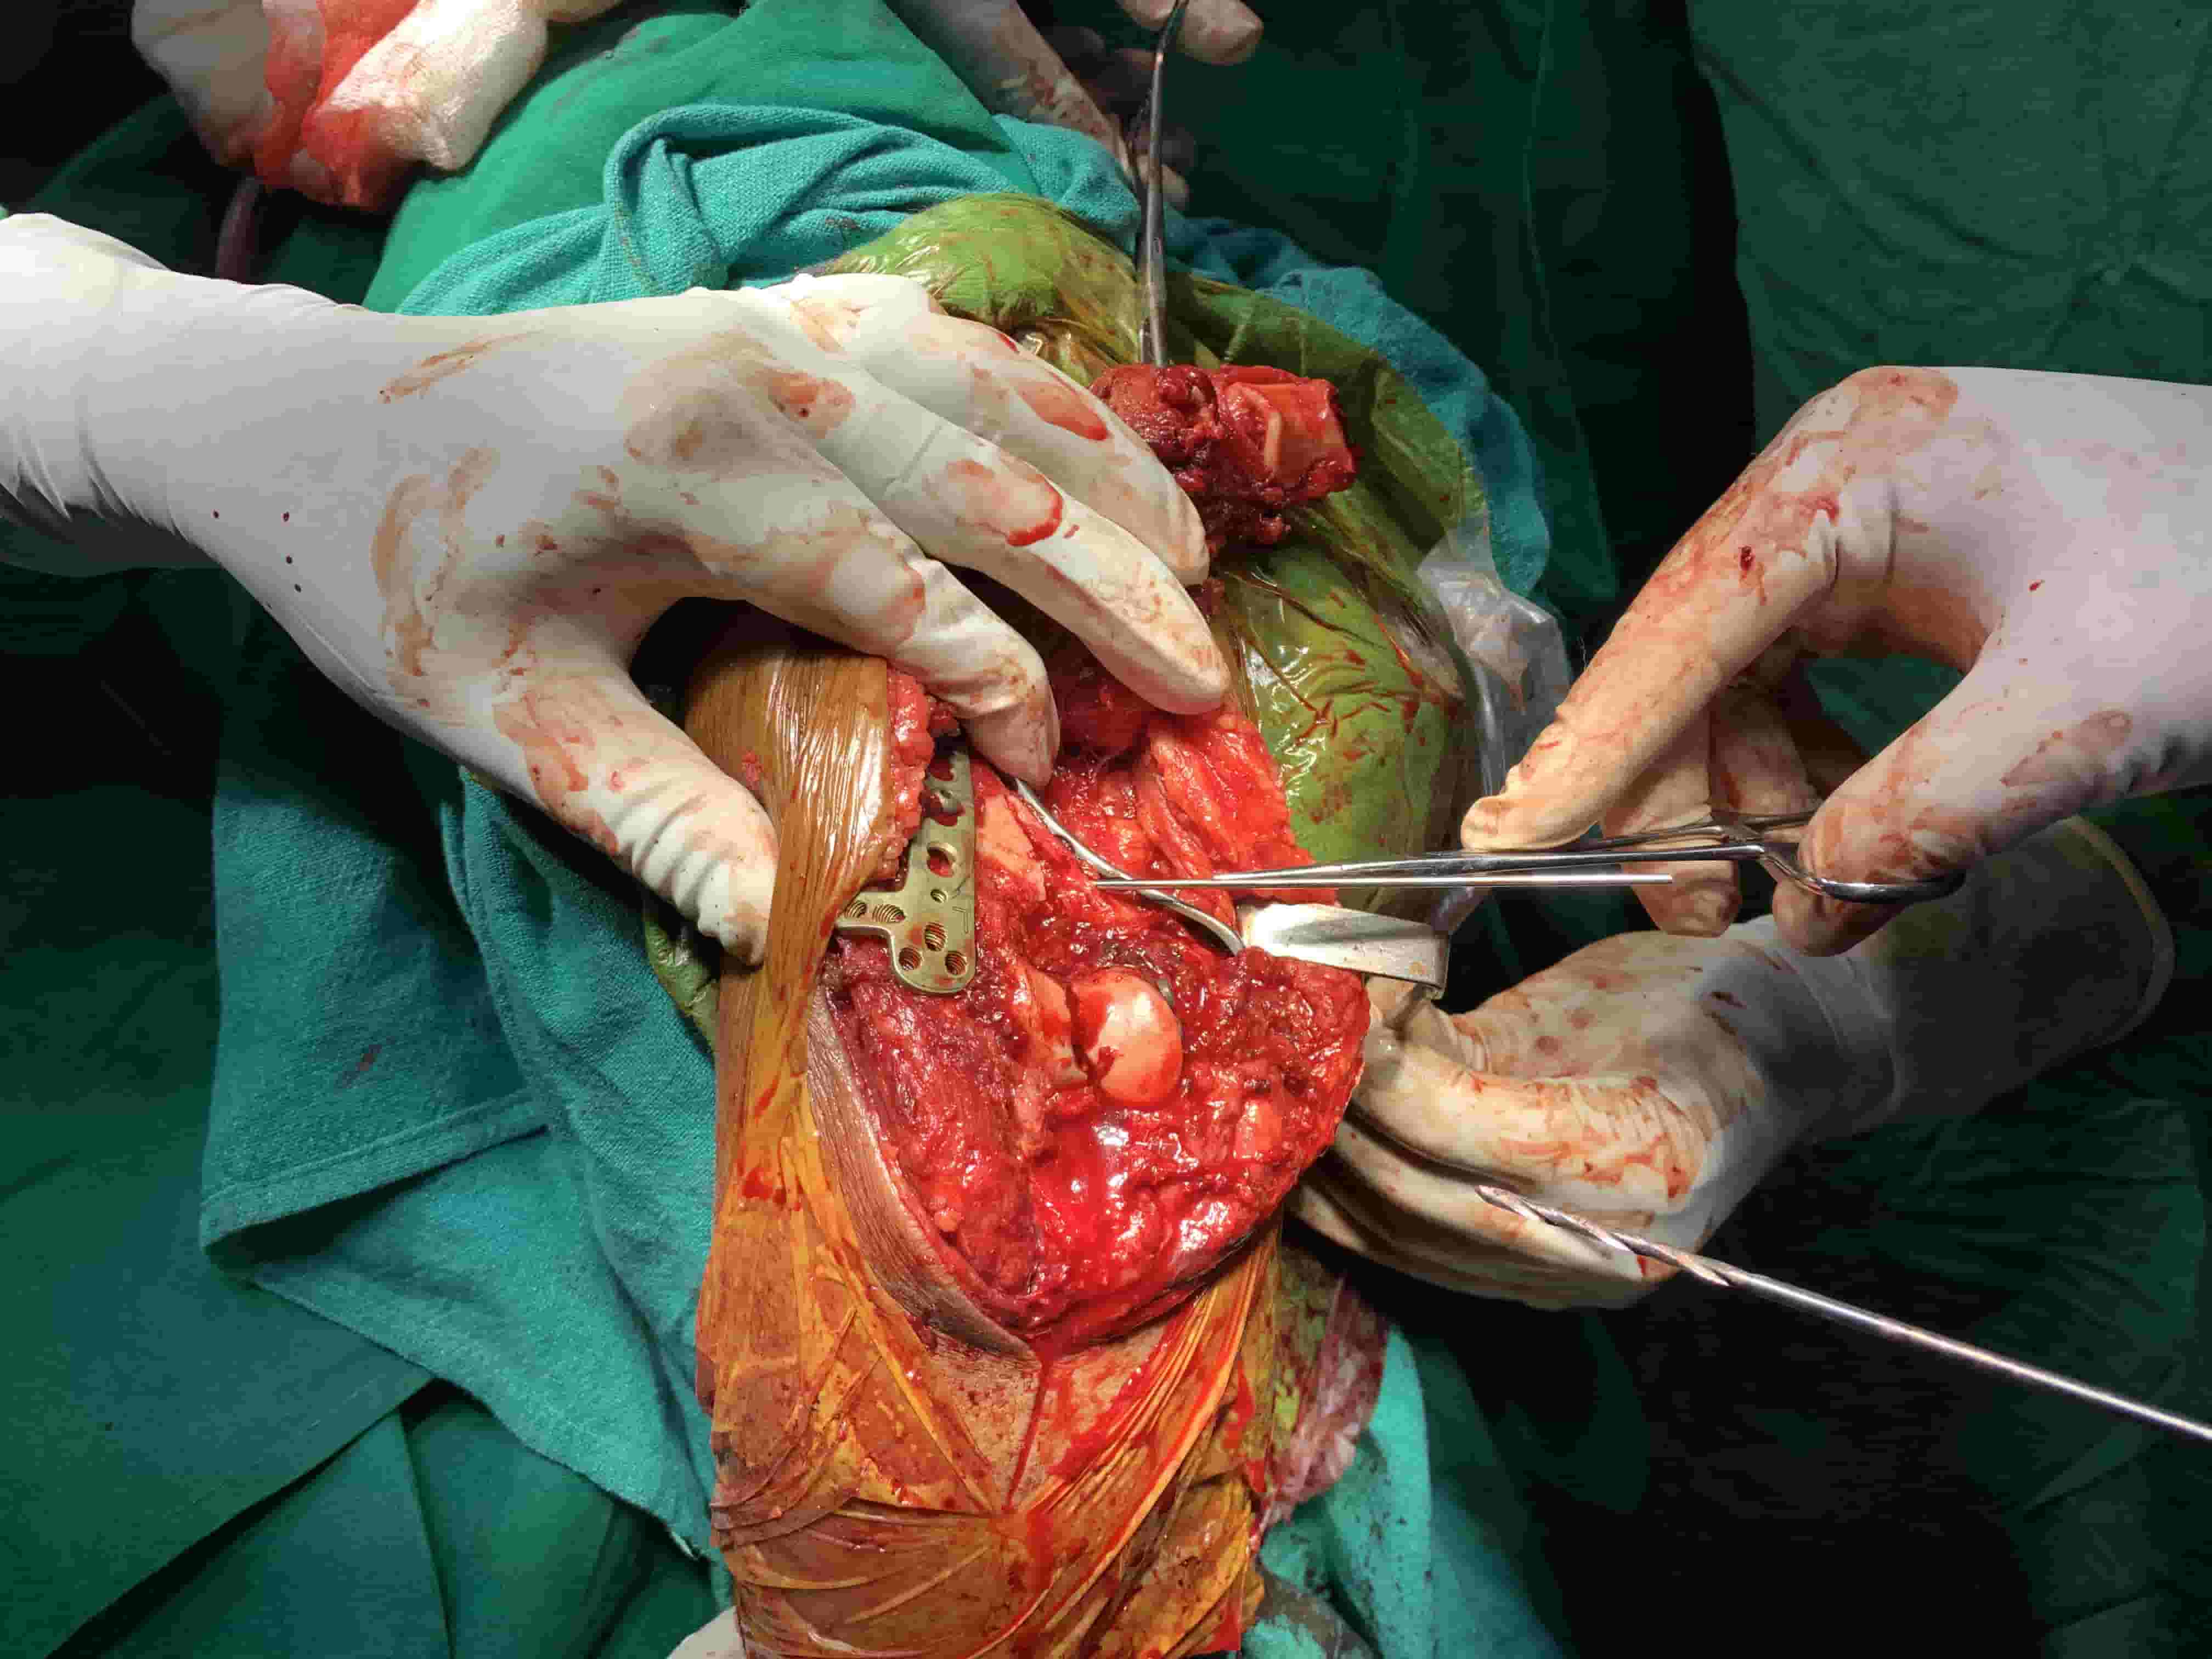

Complex Distal Humerus Comminuted Fracture

Complex Distal Humerus Comminuted Fracture

Complex Distal Humerus Comminuted Fracture

Complex Distal Humerus Comminuted Fracture

Complex Distal Humerus Comminuted Fracture

Complex Distal Humerus Comminuted Fracture

Complex Distal Humerus Comminuted Fracture

Complex Distal Humerus Comminuted Fracture

Complex Distal Humerus Comminuted Fracture

Complex Distal Humerus Comminuted Fracture

Complex Distal Humerus Comminuted Fracture

Complex Distal Humerus Comminuted Fracture

Complex Distal Humerus Comminuted Fracture

Complex Distal Humerus Comminuted Fracture